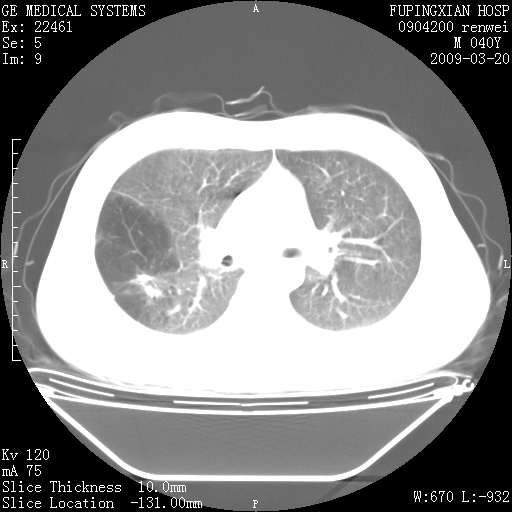

标题: CT18920:平时体健,体检时发现以下问题。 [打印本页]

标题: CT18920:平时体健,体检时发现以下问题。

单侧肺气肿表现,原因?   特发性或先天性可能

右肺气肿。

右肺局限性肺气肿

右肺局限性肺气肿。

双肺弥漫磨玻样改变,肺纹理增重,考虑早期间质纤维化伴局部阻塞肺气肿,[考虑黏液栓]

右肺局限性肺气肿;[考虑黏液栓]所致。

双肺弥漫磨玻样改变,右肺局限性肺气肿。病人没有症状?

考虑间质性肺炎伴右侧局限性肺气肿,

先天性支气管闭锁

右肺局限性肺气肿,原因?先天支气管闭锁?粘液栓?